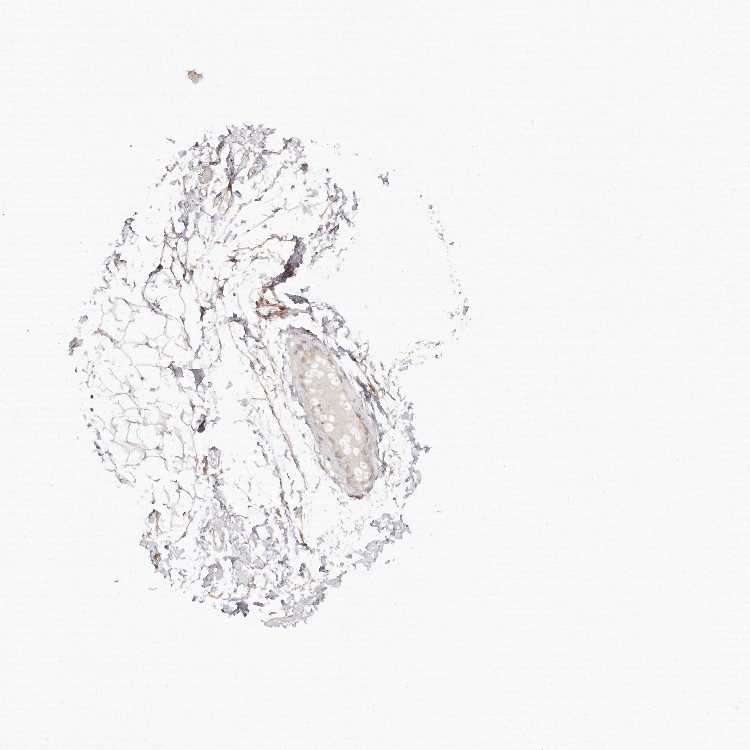

SOFT TISSUE 1 - Antibody stainingi

Antibody staining in the annotated cell types in the current human tissue is reported as not detected, low, medium, or high, based on conventional immunohistochemistry profiling in selected tissues. This score is based on the combination of the staining intensity and fraction of stained cells.

Each image is clickable and will lead to virtual microscopy that enables deeper exploration of all samples and also displays staining intensity scores, fraction scores and subcellular localization as well as patient and tissue information for each sample.

Antibody HPA027091

Fibroblasts Not detected

SOFT TISSUE 2 - Antibody stainingi

Fibroblasts Low